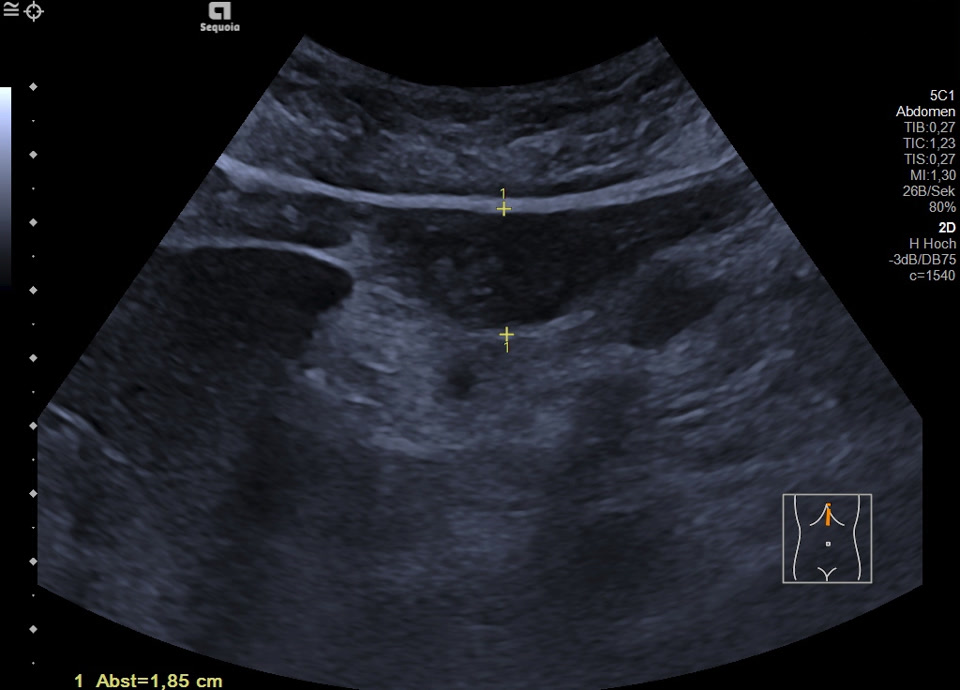

Es zeigt sich subkapsulär in Segment VI der Leber eine zystische Raumforderung mit durchgehendem Kapselreflex und hyperechogenem solidem Anteil. Der Befund ist nicht vereinbar mit einer blanden Zyste, sondern suspekt auf eine zystisch-solide Metastase. In der ergänzenden CEUS nehmen die soliden Anteile in der arteriellen Phase Kontrastmittel auf und zeigen in den portalvenösen sowie späten Phasen eine persistierende KM-Anreicherung ohne Washout. Zusätzlich finden sich eine noduläre Peritonealverdickung im Oberbauch sowie ein zystischer Ovarialtumor mit soliden Anteilen im rechten Unterbauch. In Zusammenschau der Befunde besteht der dringende Verdacht auf ein hepatisch und peritoneal metastasierendes Ovarialkarzinom.